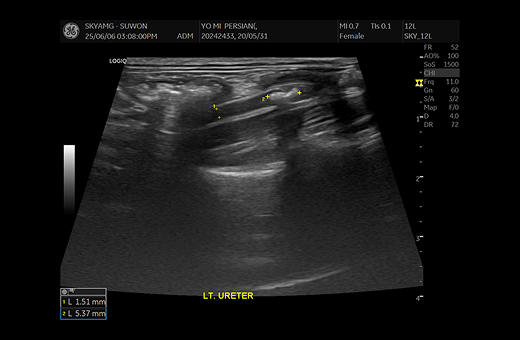

1-1 1-2

요관 확장으로 인해 SUB 수술적 치료 진행

2-1 2-2

요관 내에 결석 여러 개 관찰된 모습

· 초음파 검사

초음파 검사를 통해서 요관의 확장 정도와, 결석의 위치 등에 대한 정보를 확인하게 되며, 이로 인한 폐색에 따른 신우 확장 정도를 평가하게 됩니다. 신우 확장이 명확하고, 결석의 위치 정보 등이 확인되면, 수술적인 치료를 통한 폐색의 해소를 목표하게 됩니다.